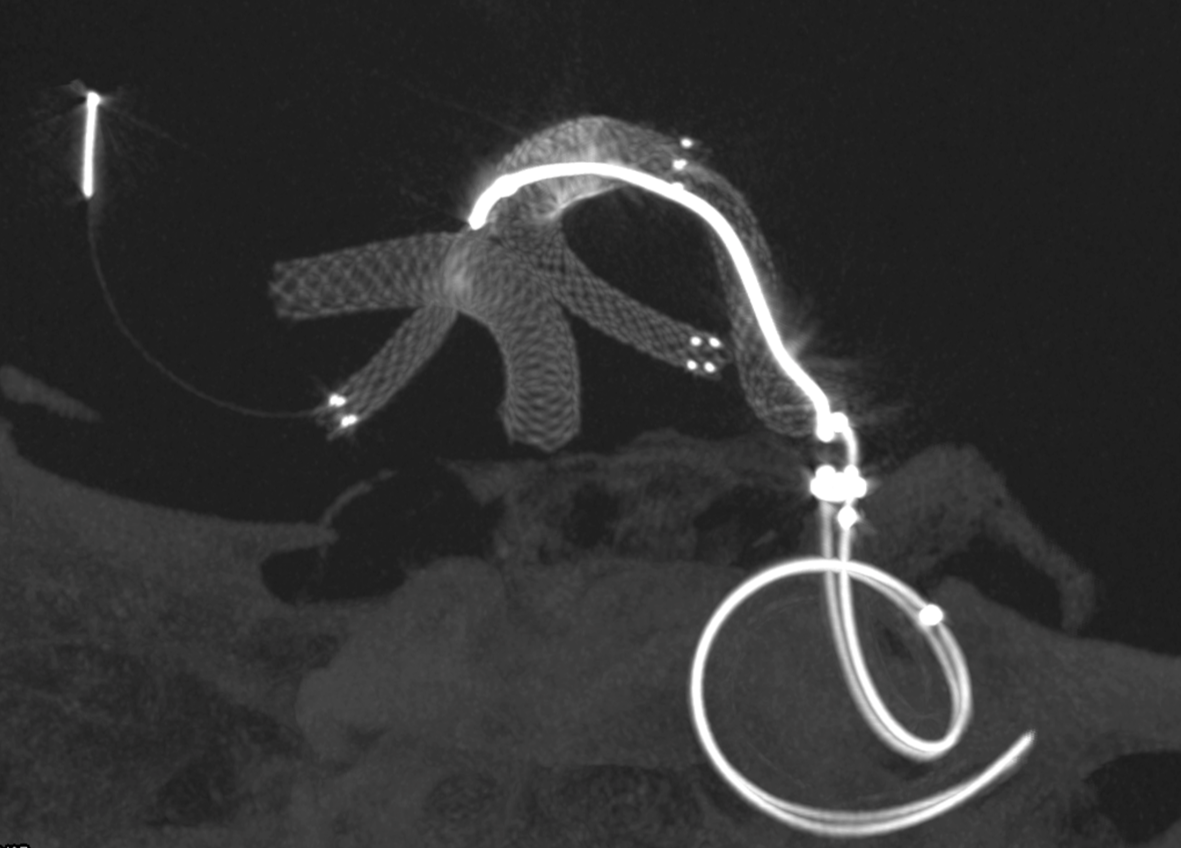

Noncontrast / dry Vaso-CT, 22 cm FOV 20 seconds acquisition, followed by a secondary reconstruction with 50% FOV and 5123 resolution; Thick MIP.

We can clearly see the three stents. The Credo seems too rigid and probably is not fully open in the curve. The Bentley (arrows) is a little bit overinflated (consider that at this level the coils reduce the image quality). SV is open with some irregularity.

This is the problem with using laser-cut stents for fishmouthing. Alternative is a relatively low coverage braided stent like Evo or LVIS Jr.